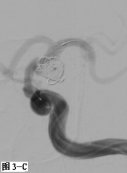

图3 采用支架辅助双微导管技术栓塞左侧颈内动脉后交通段不规则形态动脉瘤。A.DSA显示囊性动脉瘤破裂后在瘤体顶端又形成一假性动脉瘤;B.工作角度发现该动脉瘤瘤颈宽,颈内动脉直接成为瘤颈一部分;C.在部分释放支架情况下,交替填塞微弹簧圈;D.动脉瘤填塞致密,载瘤动脉通畅。